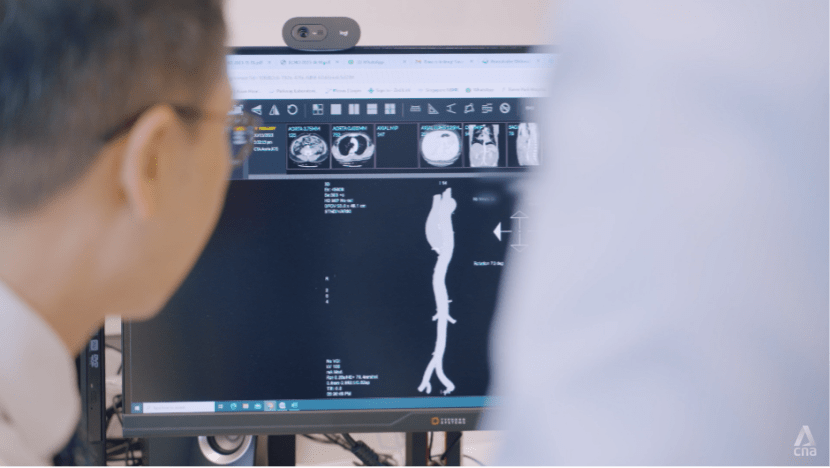

Before deciding which type of surgery is best suited for the patient, cardiac imaging tests such as echocardiograms or CT scans will have to be done.

“The collaboration between the surgeon and imaging cardiologist can help reduce the risk of the complications related to procedures and actually choose the best methods for a better outcome and decrease the risk of the complications,” says Dr Wong.